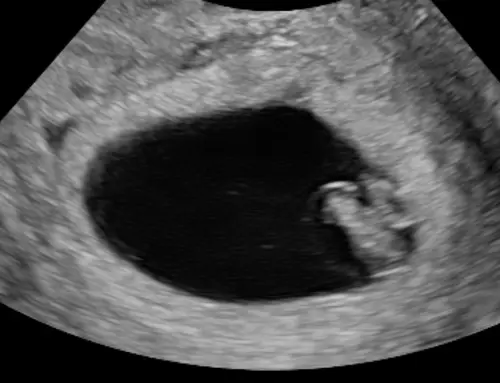

Heb je kunnen vragen aan je gynecoloog waar de placenta ligt? Volgens ramzi theorie

Op Inwendige echo: links meisje rechts een jongen

Op Uitwendig omgekeerd.

Als ik me goed begrijp he natuurlijk..😅😅

Of je kan anders ramzi theorie opzoeken?😁 Laat mij weten als je een antwoord hebt 😉😉

Volgens de foto en de ramzi theorie denk ik en ik ga mijn mening veranderen. Dus de baby zal een jongen zijn? 😅😅